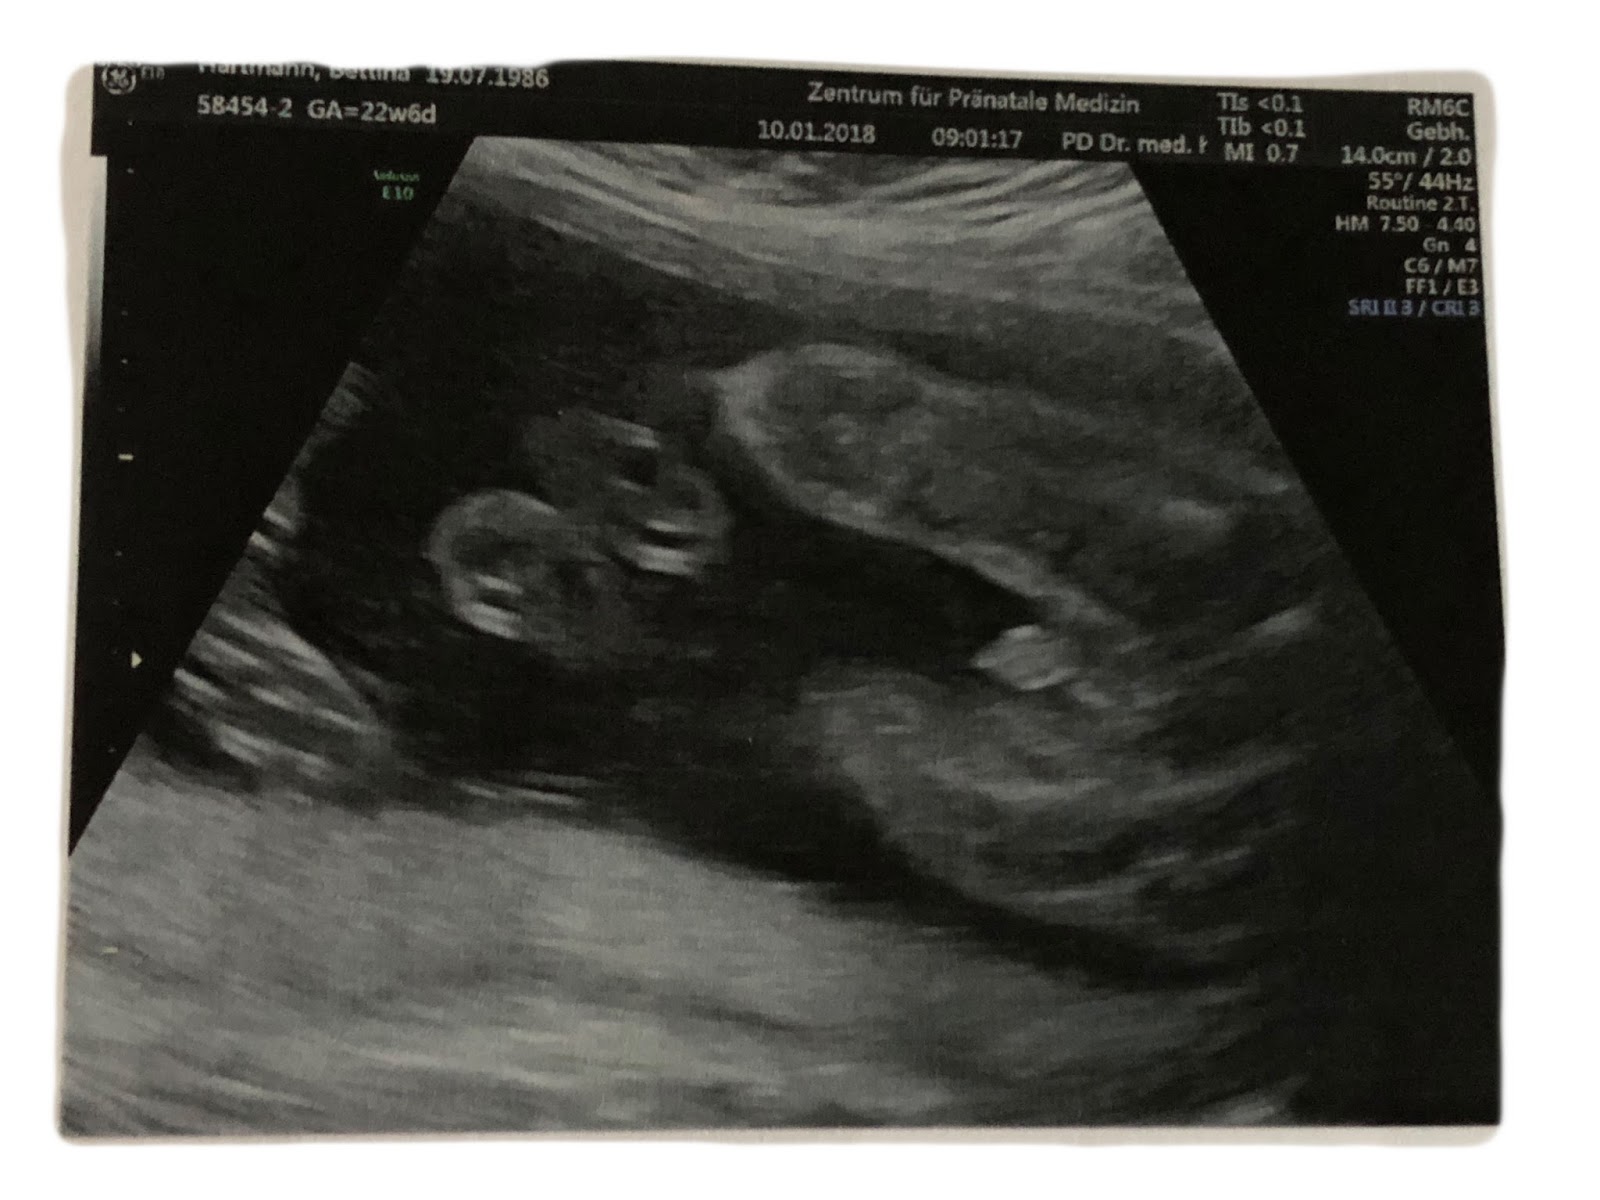

Ein wunschgeschlecht für ihr baby haben die meisten. Ob junge oder mädchen. Anzeichen für junge oder mädchen die bekanntesten mythen. Dann lies dir am besten die folgenden 10 anzeichen durch. Relativ sicher beantworten lässt sich die frage mädchen oder junge bei der zweiten regulären ultraschalluntersuchung zwischen der 19. Monat video 1 duration. Vielleicht trifft davon etwas auf dich zu oder hilft dir das geheimnis zu lüften.

Wenn sie wissen wollen ob sie einen jungen oder ein mädchen erwarten müssen sie mindestens bis woche 17 ausharren. Ssw besonders im 3d ultraschall vorausgesetzt das kleine dreht und krümmt sich nicht so dass der arzt nichts erkennen kann. Noch bevor dein baby organe einen herzschlag oder ein gehirn hatte war das zukünftige geschlecht bereits teil der genetischen information. Ssw 17 0 tage ssw 17 1 tag ssw 17 2 tage ssw 17 3 tage ssw 17 4 tage ssw 17 5 tage ssw 17 6 tage.